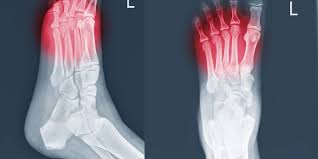

• Fracturas por Estrés: Pequeñas fisuras en los huesos debido a la sobrecarga.